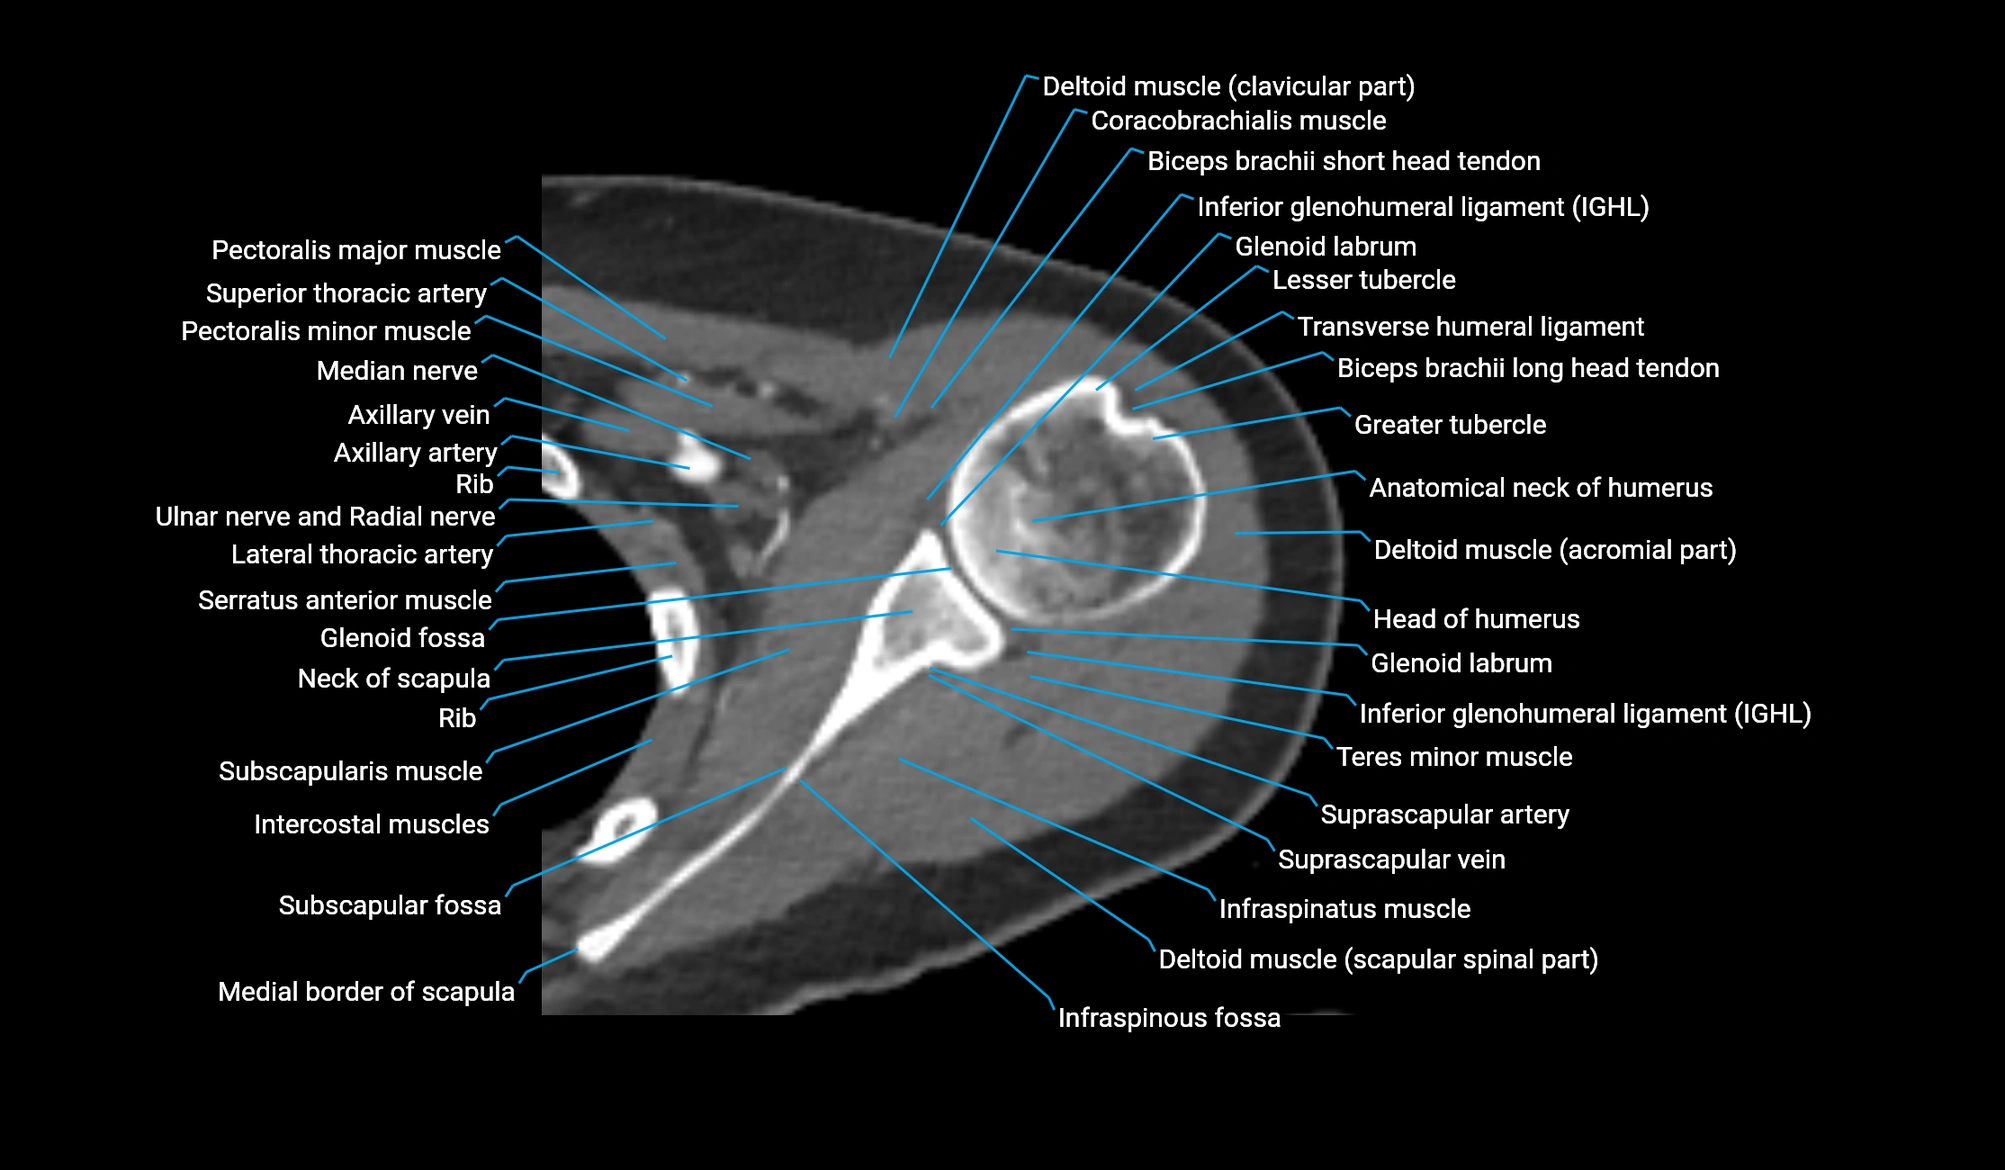

- Anatomical neck of humerus

- Glenoid labrum

- Head of humerus

- Inferior glenohumeral ligament

- Infraspinatus muscle

- Infraspinous fossa

- Lesser tubercle of humerus

- Neck of scapula

- Pectoralis major muscle

- Pectoralis minor muscle

- Scapular spinal part of deltoid muscle

- Subscapular fossa

- Subscapularis muscle

- Teres minor muscle